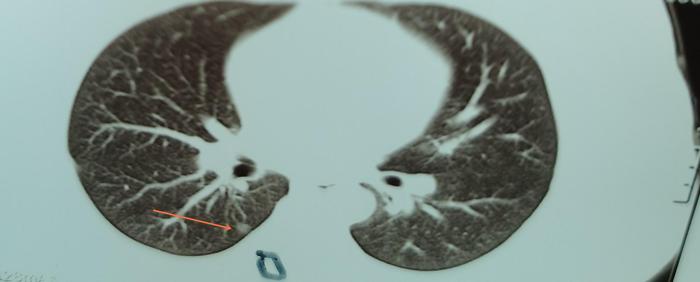

下图为一个高一孩子的右下肺纯磨玻璃结节,大约7毫米,看起来像原位癌。